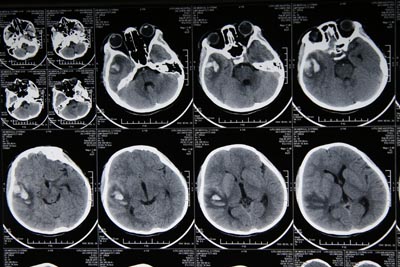

大年三十晚上,十岁女童贾某在无成人陪护的情况下,燃放了一枚威力不小的爆竹,而导致爆竹伤及头部,右颞红肿、出血,被送往当地医院进行了包扎处理。原以为慢慢恢复即可康复,但是,连续两天患者出现了头晕、头疼、恶心、呕吐等症状,为求进一步诊治,于大年初三送来我院神经外科就诊。主管大夫权俊杰医师经脑CT检查,确诊为急性闭合性颅脑损伤、脑挫裂伤(右颞)、软组织挫伤(右颞、右眼睑),收治入院进行药物保守治疗,目前患者正在进一步康复中。